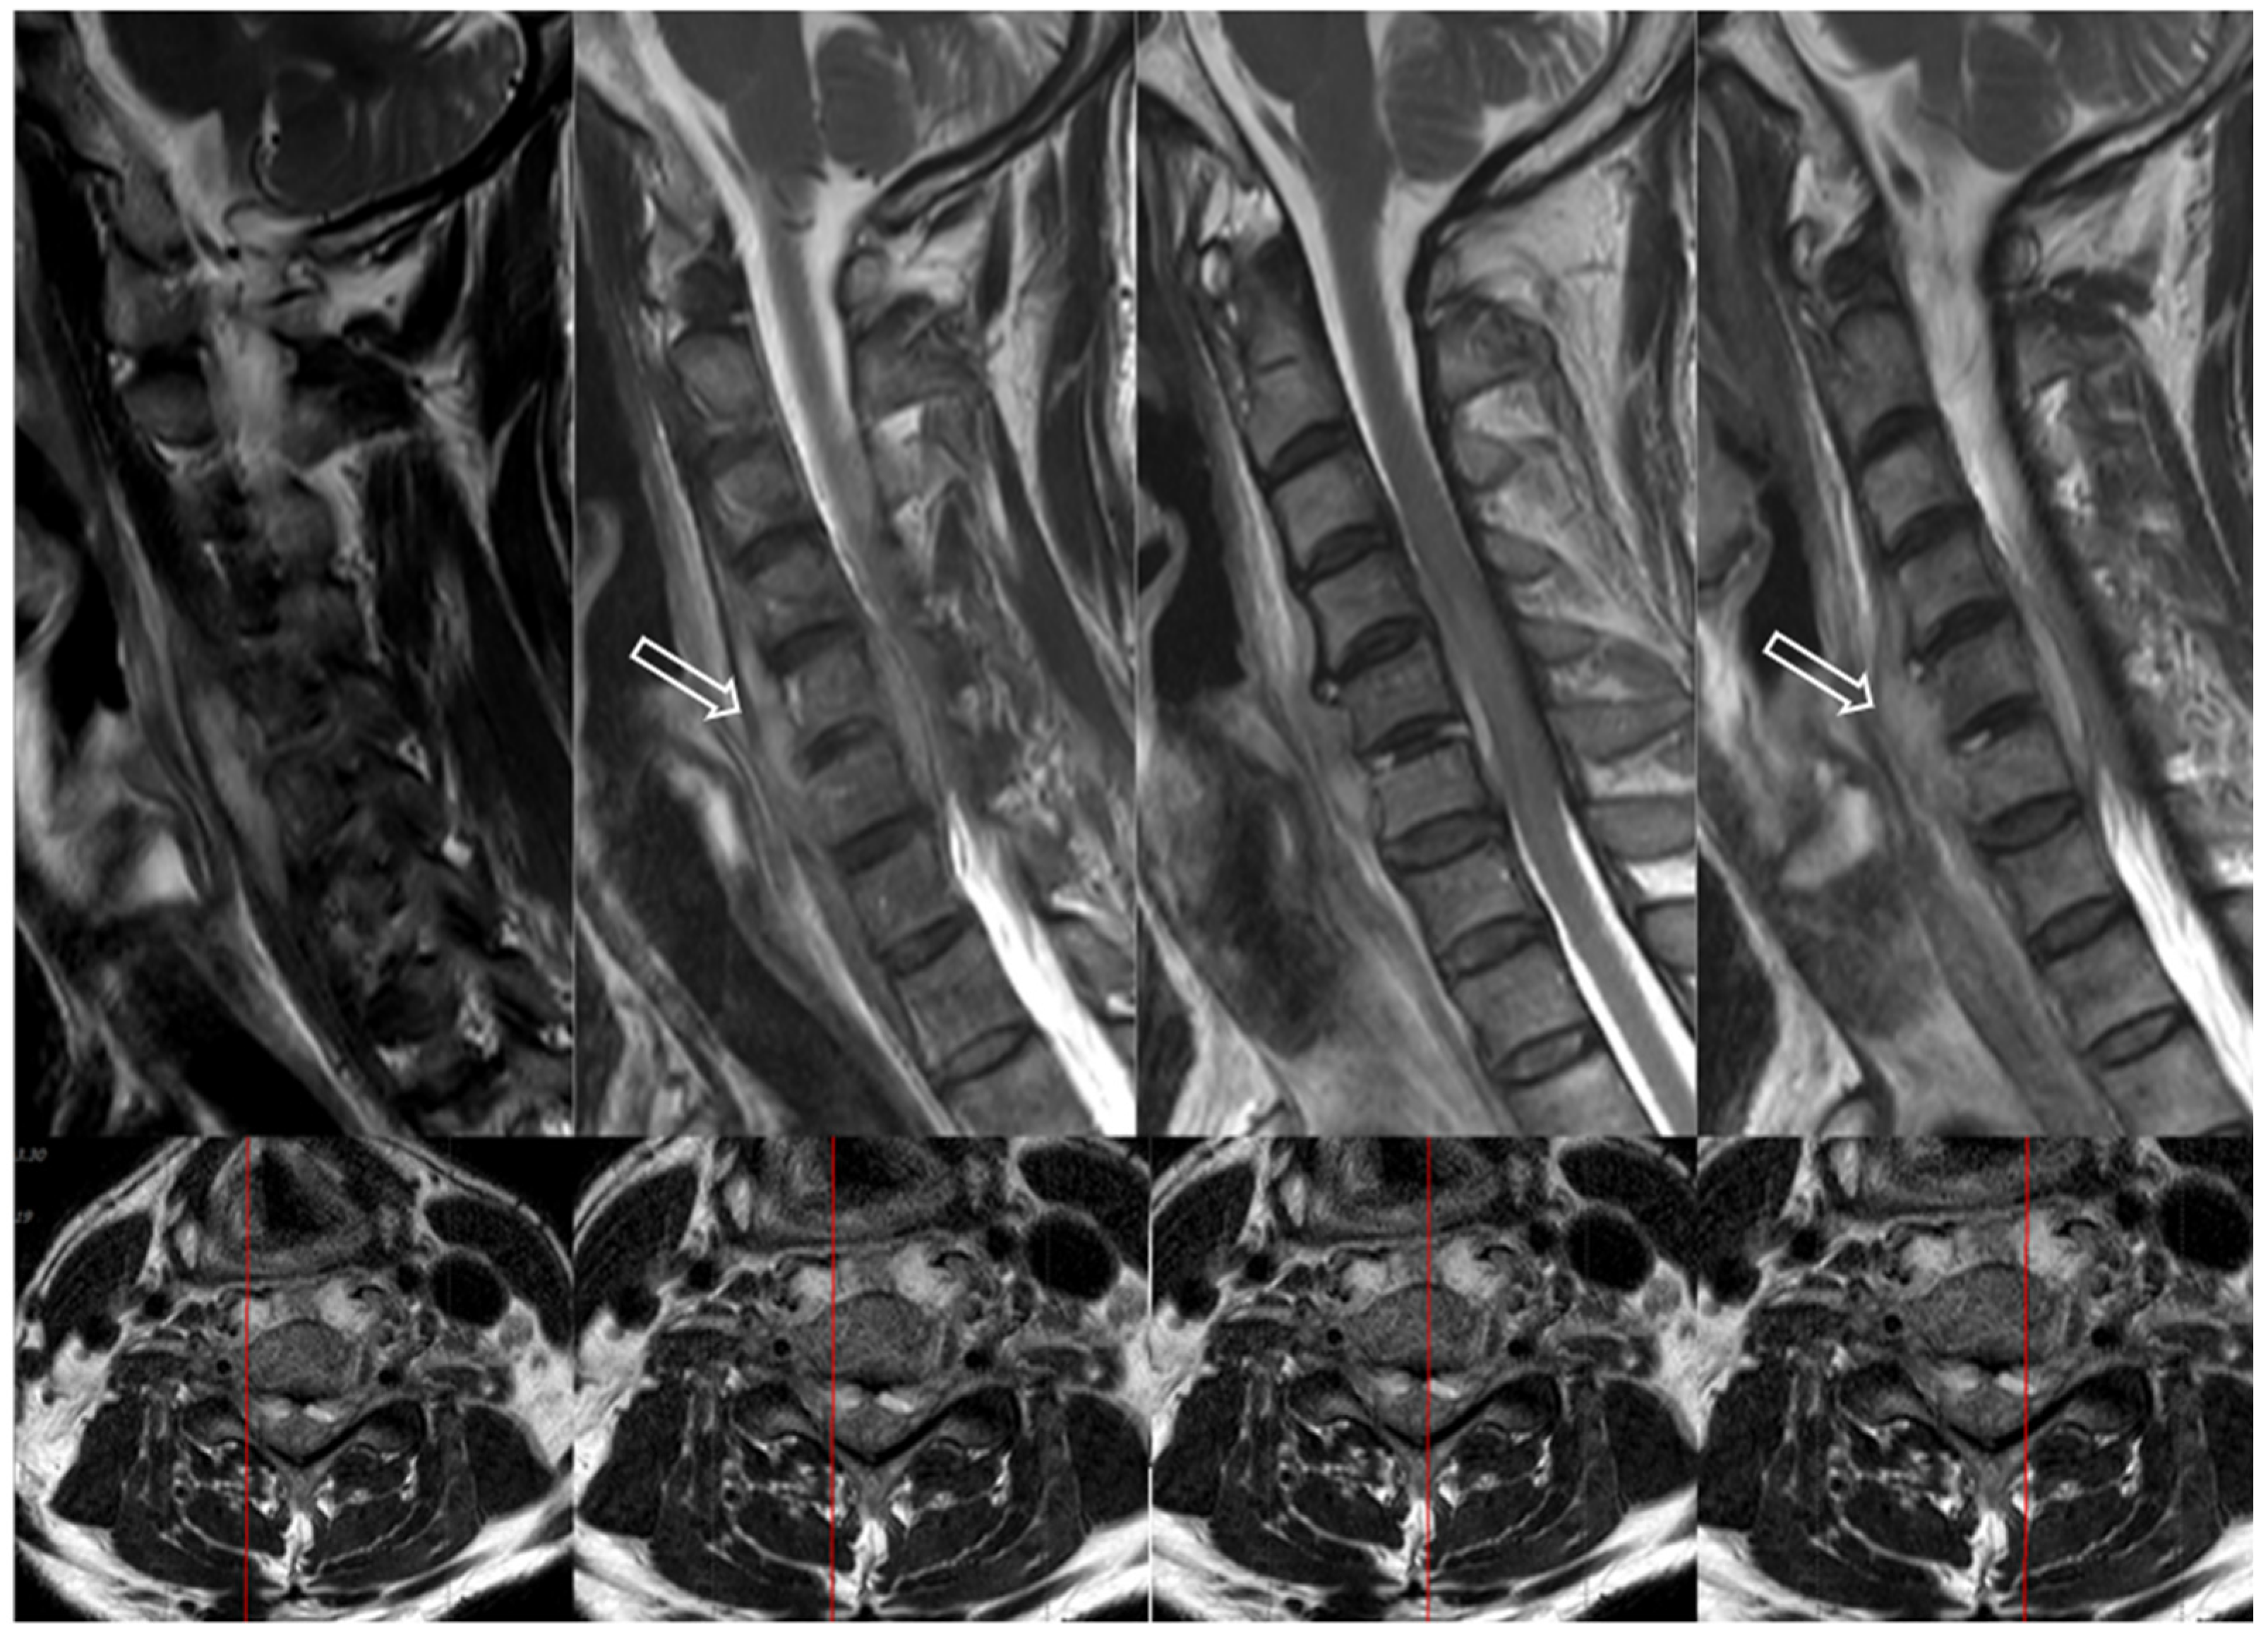

7.3. Imaging Tests

- Modic, M.T.; Feiglin, D.H.; Piraino, D.W.; Boumphrey, F.; Weinstein, M.A.; Duchesneau, P.M.; Rehm, S. Vertebral osteomyelitis: Assessment using MR. Radiology 1985, 157, 157–166. [Google Scholar] [CrossRef] [PubMed]

- Mavrogenis, A.F.; Megaloikonomos, P.D.; Igoumenou, V.G.; Panagopoulos, G.N.; Giannitsioti, E.; Papadopoulos, A.; Papagelopoulos, P.J. Spondylodiscitis revisited. EFORT Open Rev. 2017, 2, 447–461. [Google Scholar] [CrossRef]

- Sans, N.; Faruch, M.; Lapègue, F.; Ponsot, A.; Chiavassa, H.; Railhac, J.J. Infections of the spinal column—Spondylodiscitis. Diagn. Interv. Imaging 2012, 93, 520–529. [Google Scholar] [CrossRef] [PubMed]

- Sharif, H.S. Role of MR imaging in the management of spinal infections. AJR Am. J. Roentgenol. 1992, 158, 1333–1345. [Google Scholar] [CrossRef]

- Stäbler, A.; Reiser, M.F. Imaging Of Spinal Infection. Radiol. Clin. 2001, 39, 115–135. [Google Scholar] [CrossRef]

- Lee, J.S.; Suk, K.S.; Kwon, J.W.; Moon, S.H.; Ju, H.J.; Lee, B.H.; Abdou, M. Cervical transpedicular irrigation and drainage in a patient with cervical spondylodiscitis after hypopharyngeal cancer treatment: A case report. J. Clin. Med. Images 2023, 4. [Google Scholar]